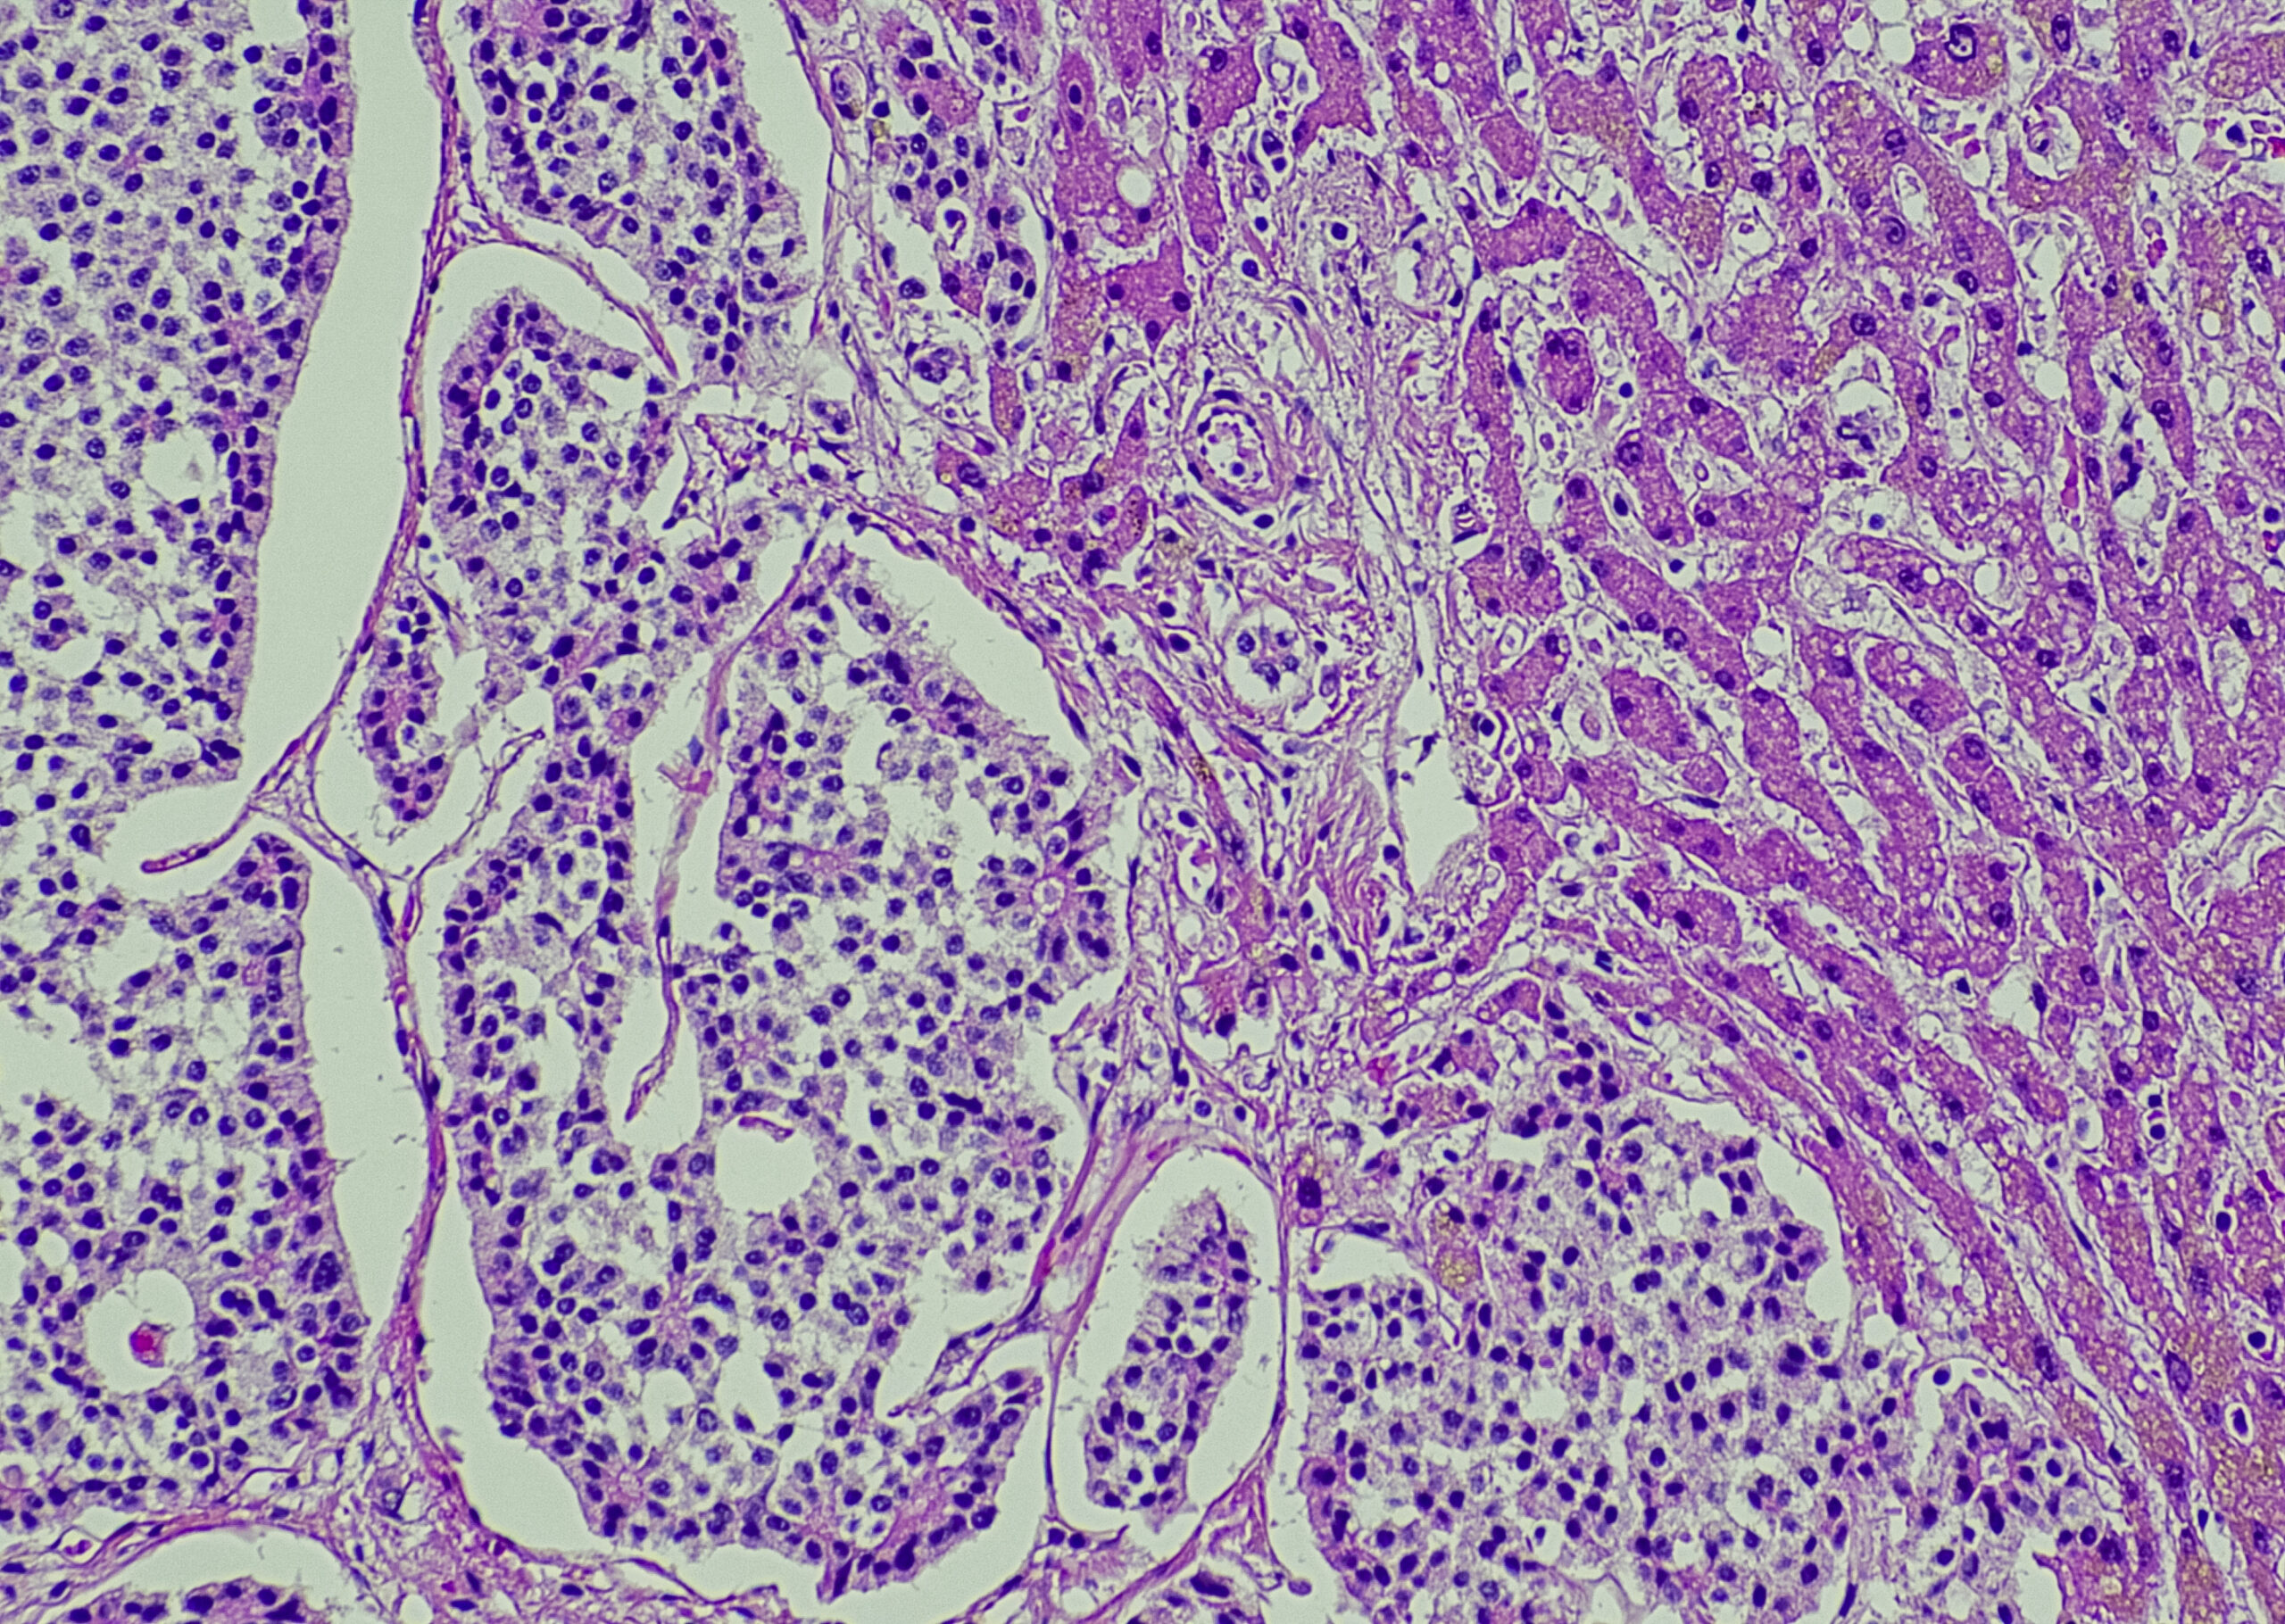

Komplizierte Nierenzysten